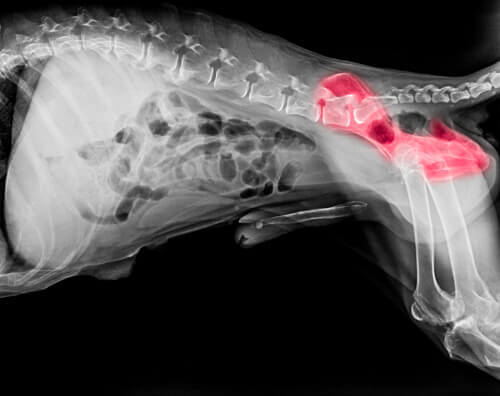

A displasia do quadril talvez seja a doença mais comum em pastores alemães. Tem origem hereditária, embora outros fatores, como falta de exercícios ou dieta inadequada, também influenciem. A displasia é uma doença degenerativa caracterizada pelo encaixe incorreto da cabeça do fêmur no quadril. Isso faz com que o fêmur se desloque, causando claudicação e osteoartrite a longo prazo.